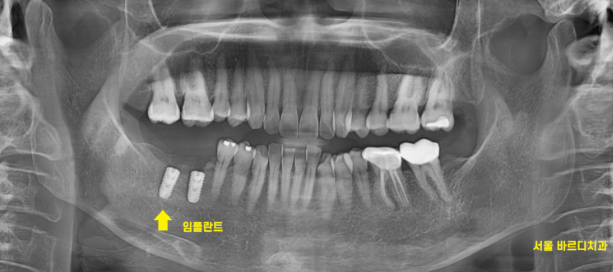

겉으로 봤을 때는 잇몸만 느껴지지만

x-ray를 보실까요~?

230717

임플란트가 잘 심어져있습니다.